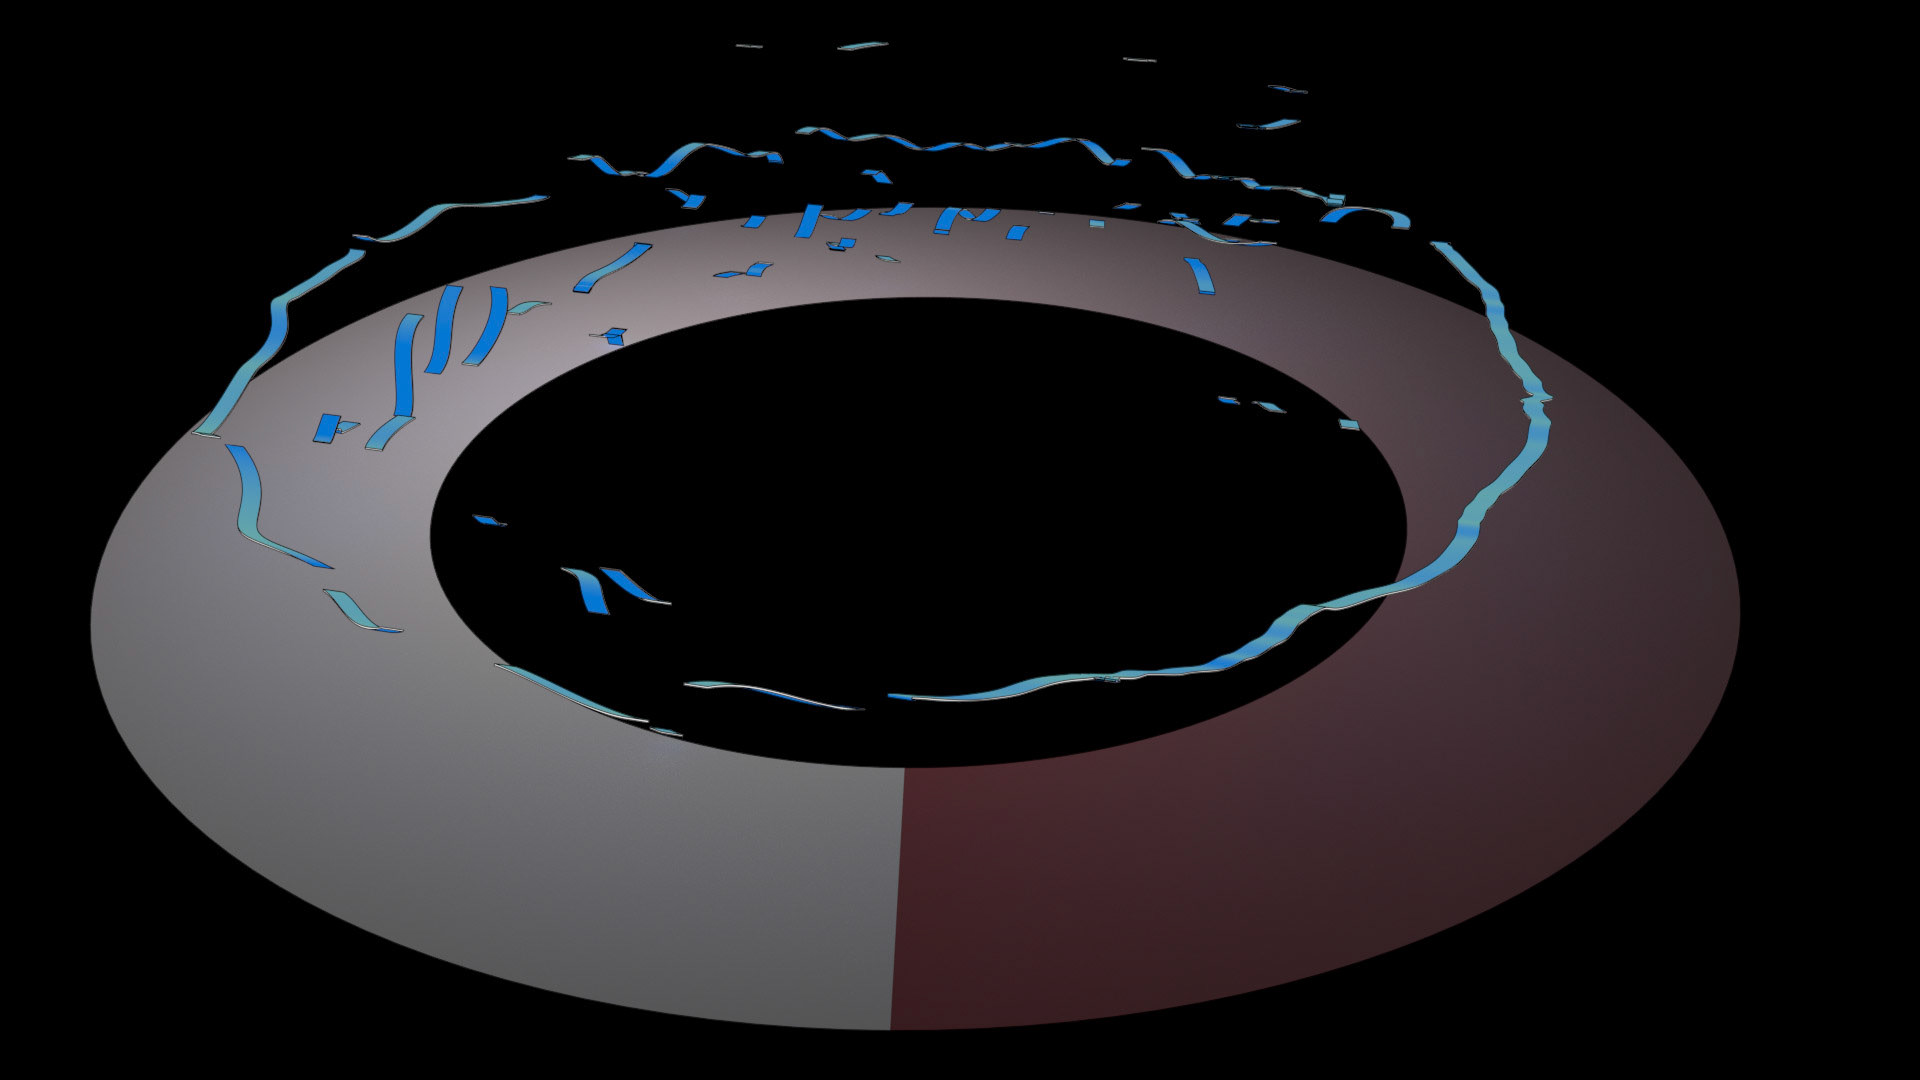

An ongoing collaboration with the Biomedical Simulation Lab (BSL), University of Toronto. In my role, I develop concept sketches and renderings that are then implemented algorithmically. The overall approach is to show turbulent flow visualizations without animation my mapping the transitions among states to carousel that corresponds to the cardiac cycle.